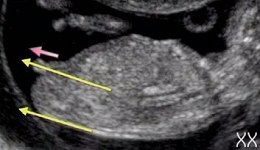

Мальчик или девочка?? Узист сказал сначала девочка потом 50/50; 12-13 недель

Посмотрите у меня в дневнике, тоже задавала такой вопрос. У нас девочка в итоге. Мне кажется, мальчик у вас. У вас видна и пуповина и писюлька. У писюльки угол больше 30 градусов..))))

Я посмотрела) больше 30градусов думаете? Говорят когда к вверху мальчик к низу девочка) может он чуть не так лежит☺️